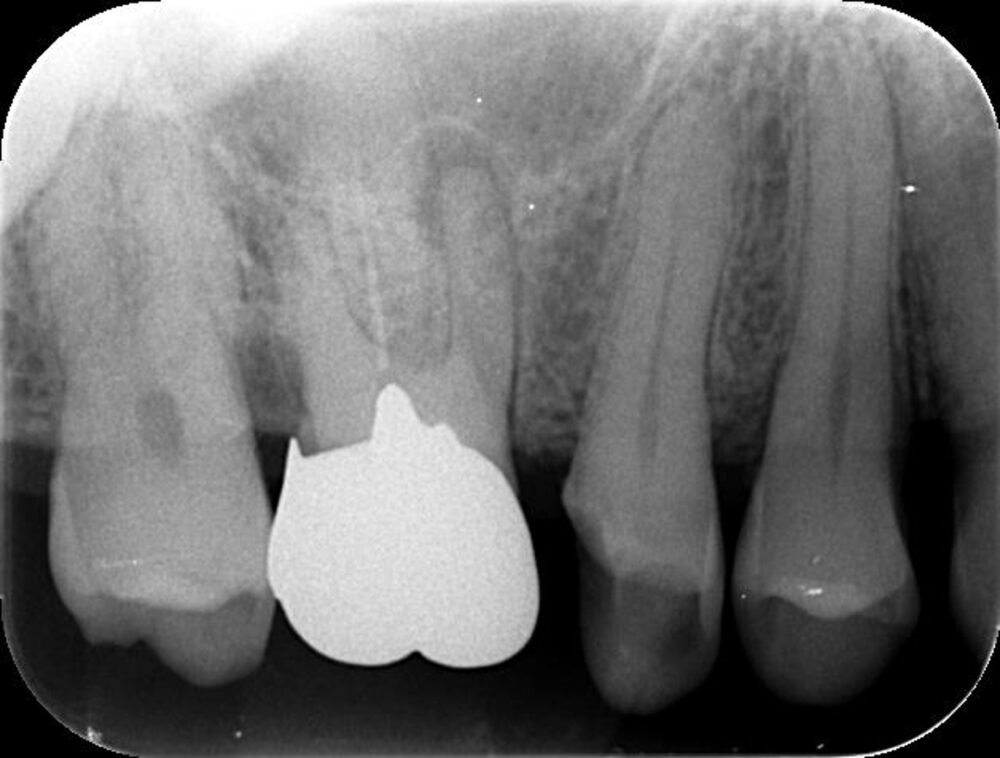

症例1:パーフォレーションリペア症例

(歯の中に大きな穴が空いてしまっているのを埋めて再生を促す治療)

歯に穴が空いていて骨に炎症がある状態 |

CTでも歯の周囲に骨がないのが分かる。 |

| 医院の診断 | 虫歯の再発、慢性根尖性歯周炎、遠心根人為的穿孔 |

人為的根穿孔を起こした部分に感染を起こしており、歯周ポケットが9㎜ありました。 ラバーダム防湿とマイクロスコープを使用して丁寧に治療を行いました。 殺菌性があり歯を補強することのできるMTAという根管充填材料を使用して、歯周ポケットは2㎜に改善しました。 |